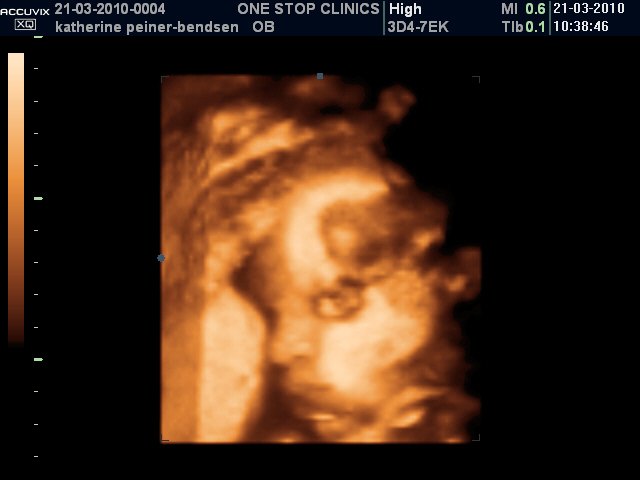

Bb3031

Scanningsbilleder af Alexander taget i uge 31.

Han puttede sig godt ind mod moderkagen med sin højere side af ansigtet, så vi fik desværre aldrig et fuldt profilbillede af den lille gut  Men tilgengæld oplevede vi, at han åbnede sine øjne en del gange og blinkede til os

Vedhæftede fotos (klik for at se i fuld størrelse)